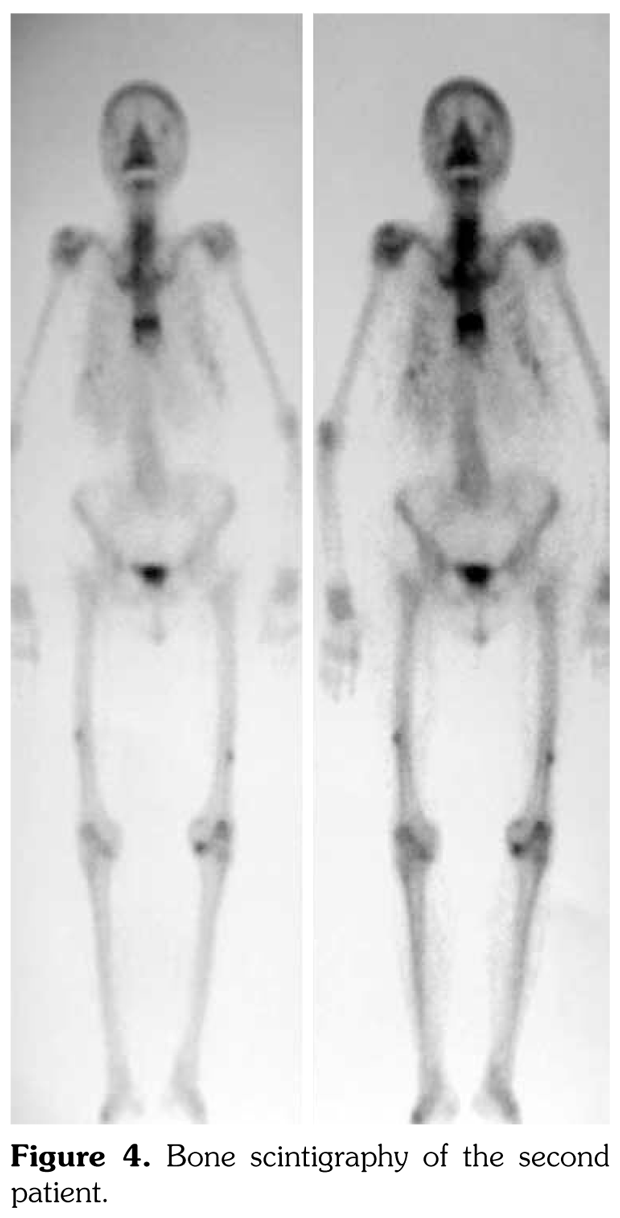

Case 2– A 61-year-old female patient presented with anterior thigh pain and difficulty in walking. Pain severity was 7 over 10 point according to visual analog scale. She had been treated with alendronate 70 mg per week with calcium plus vitamin D for two years. Plain radiographs of femur were taken upon clinical presentation. Cortical stress reaction was detected in both femoral shafts on plain radiographs (Figure 2). Computed tomographic imaging was performed to rule out fracture (Figure 3). Bone scintigraphy showed increased uptake in distal (1)/3 ends of femoral shafts (Figure 4). Serum calcium value was normal and urinary deoxypiridinoline level was mildly increased (46 nM/mMCre).

Bone scintigraphy of the patients revealed increased uptake in femoral diaphysis. Atypical bisphosphonate associated subtrochanteric and femoral shaft stress fractures show specific appearance on bone scintigraphy characterized by mild uptake in multifocal endosteal thickening of the lateral femoral diaphysis.(11)